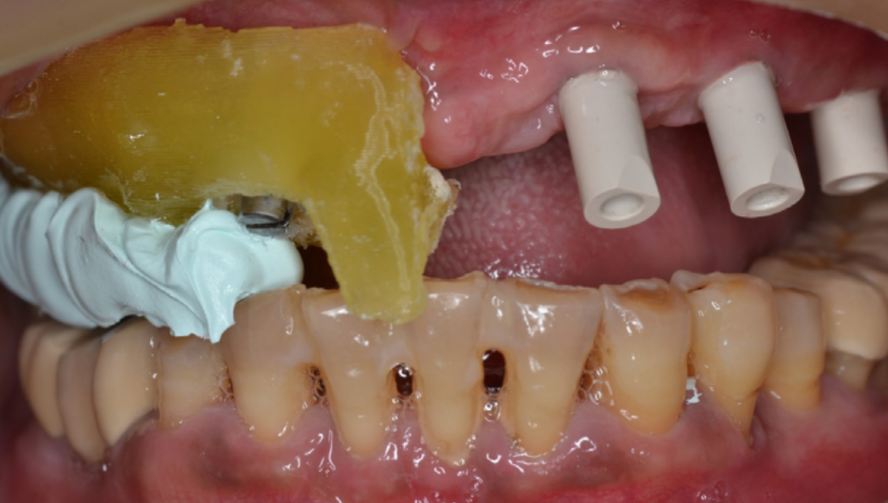

Після встановлення імплантів, верхньощелепний знімний протез було оброблено препаратом Viscogel та повернено пацієнту разом з інструкцією по дотриманню гігієни ротової порожнини та розробленою дієтою. (зображення 6)

6

Щоб записати висоту прикусу, вже визначену негайним протезом, металеві штирі було видалено з шаблону та шаблон для навігаційної хірургії було надійно закріплено на серединних імплантах, з використанням модифікованих тримачів для імплантів. (зображення 9)

9

Щоб полегшити процес проведення цієї процедури, матеріал для зняття прикусу (Prestige Bite, Vanini, Італія), було застосовано для подальшої стабілізації центрального змикання щелеп (CR) на визначеній висоті прикусу. (зображення 10)